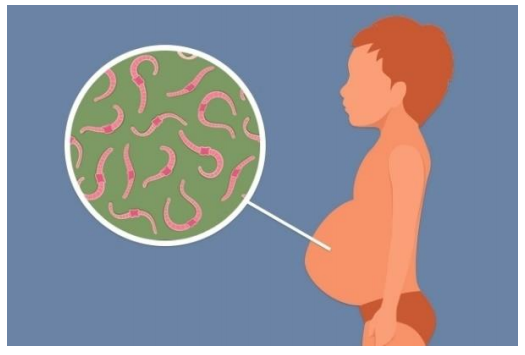

Observe a imagem a seguir:

Doença parasitária causada pelo Schistosoma mansoni. Inicialmente a doença é assintomática, mas pode evoluir e causar graves problemas de saúde crônicos, podendo haver internação ou levar à morte. No Brasil, é conhecida popularmente como “xistose” e “barriga d’água”.

O agente responsável pela transmissão dessa doença é o: